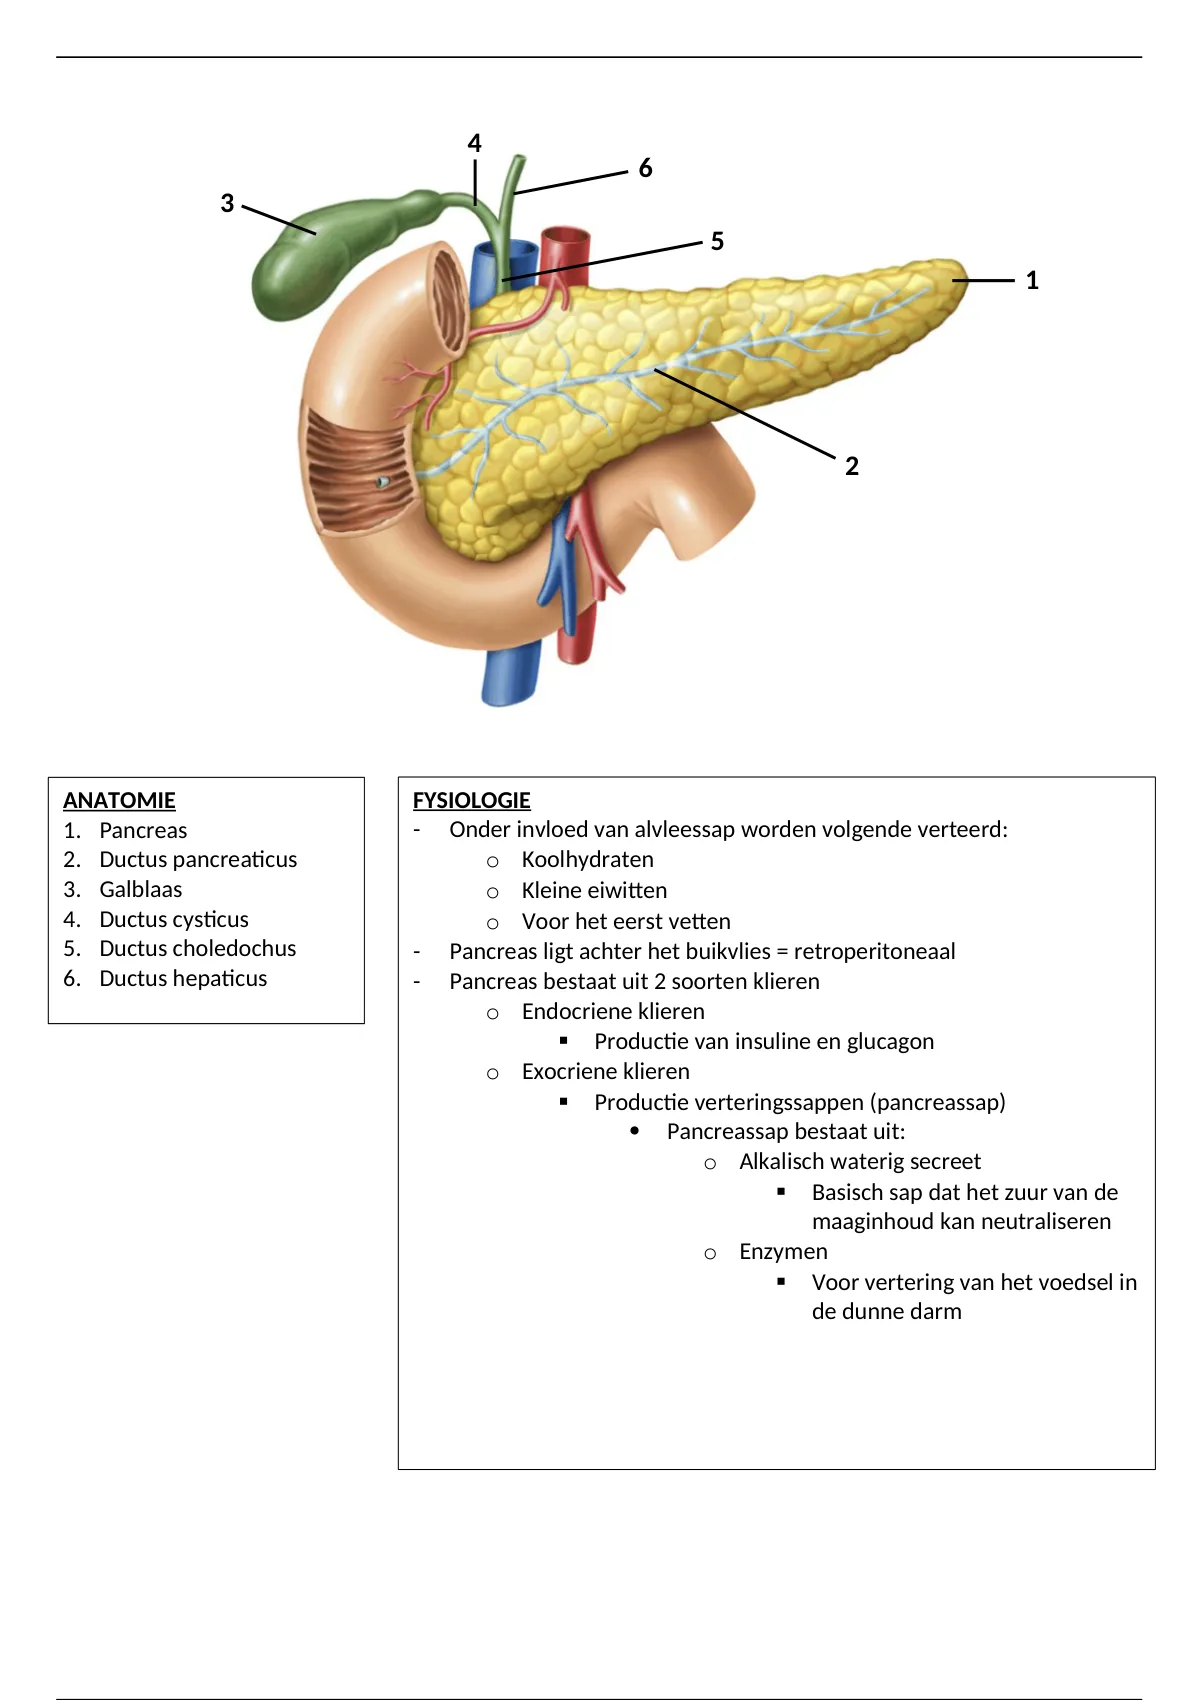

Samenvatting Anatomie en fysiologie van de pancreas en galwegen Anatomie, Fysiologie En